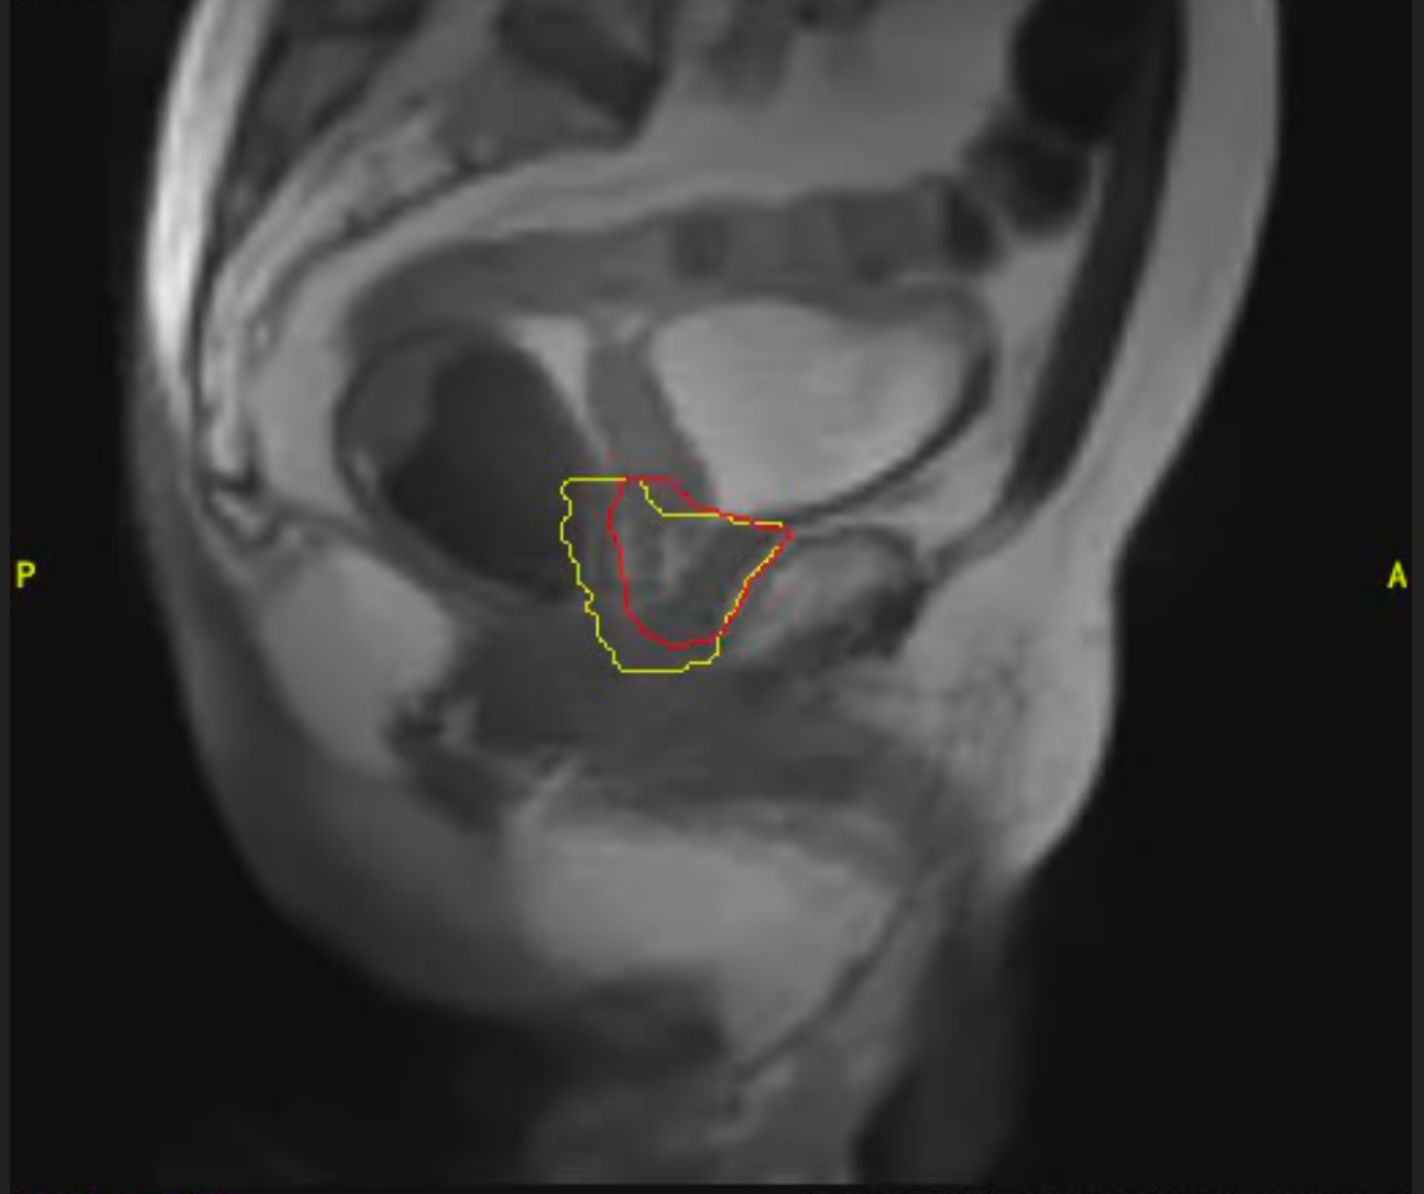

Cáncer de páncreas

Mujer de 46 años con diagnóstico de adenocarcinoma de cabeza de páncreas localizado. Recibe tratamiento con quimioterapia durante 5 ciclos y seguidamente radioterapia con intención radical en Acelerador Lineal con Resonancia (MRIdian): 5 fracciones en 5 días. Presentó buena tolerancia al tratamiento, sin efectos adversos destacables y tras 3 meses de finalizado el mismo se encuentra con enfermedad estable.

Imagen 1

Imagen 2

Imagen 3

Imagen 4